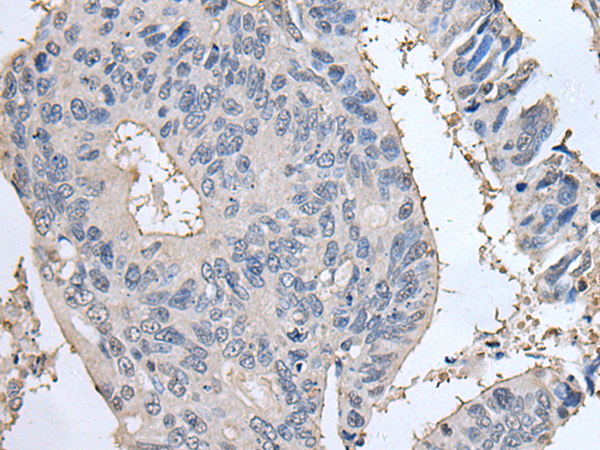

IHC positive control: |

Human colorectal cancer and human tonsil |

IHC Recommend dilution: |

25-100 |